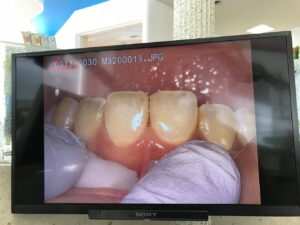

マイクロスコープを使い拡大視野で古い詰め物を取り除き、シンメトリーに新しく詰め直しました。

写真は術後

マイクロスコープにはカメラが内蔵されているので動画録画・静止画撮影が可能です。

術前・術中・術後の状態の説明や確認をモニター画面で一緒に観ることができます。